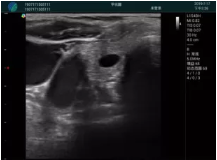

甲狀腺囊性結(jié)節(jié),囊壁鈣化,透聲好

甲狀腺囊性占位